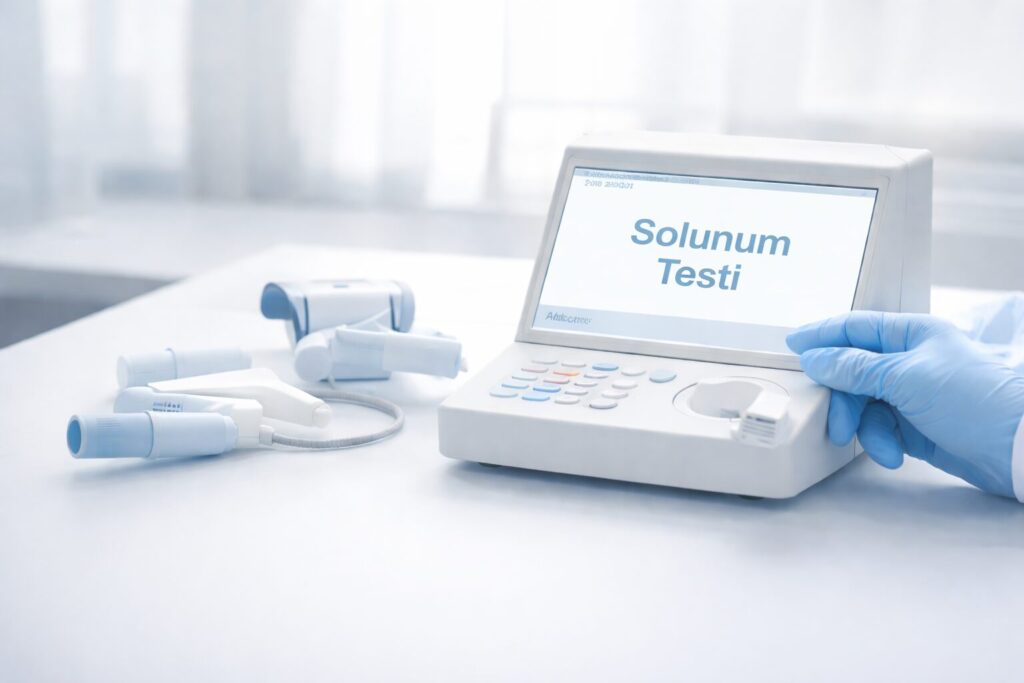

Akciğerlerimiz soluk almamızı ve hayatta kalmamızı sağlar

Uzmanlık alanım, astım, KOAH, pulmoner emboli, interstisyel akciğer hastalıkları, bronkoskopi, akciğer kanseri ve plevral hastalıklar gibi çeşitli göğüs hastalıklarını kapsar. Baltimore, Maryland, ABD’de Dr. Ko-Pen Wang’ın gözetiminde Girişimsel Pulmonoloji alanında aldığım özel eğitim ve ileri tekniklerde de girişimsel pulmonoloji becerilerimi geliştirdim.